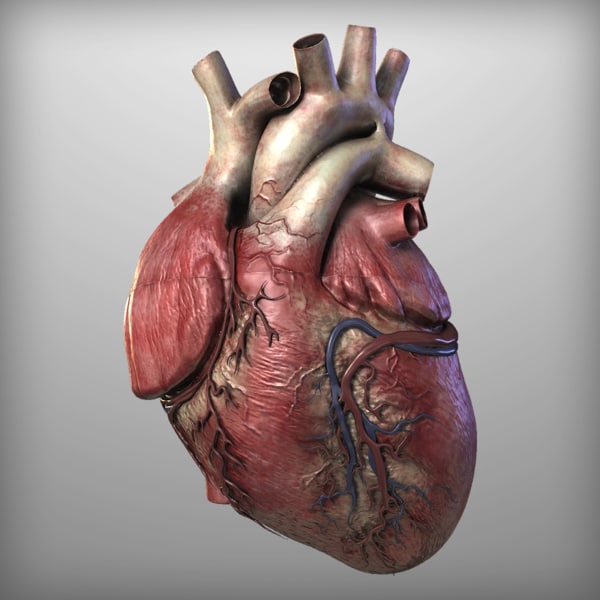

Human Heart Drawing Outline at GetDrawings | Free download  3d anatomy human heart

3d human heart  Animated Realistic Human Heart - Medically 3D asset

Animated Realistic Human Heart - Medically 3D asset  Zygote::3D Heart Model | Medically Accurate | Human Anatomy

Zygote::3D Heart Model | Medically Accurate | Human Anatomy  Zygote::Solid 3D Human Heart Model

Zygote::Solid 3D Human Heart Model  3D human heart anatomy model - TurboSquid 1283134

3D human heart anatomy model - TurboSquid 1283134  anatomy human heart 3d c4d

Human Heart Anatomy 1 3D model | CGTrader  How to draw realistic human heart||3d human heart sketch

3D Human Heart animated | CGTrader  How the Human Heart Works | Safety and Health Solutions

Realistic Human Heart 3D model | CGTrader  anatomy human heart 3d c4d

Human Heart Anatomy 1 3D model | CGTrader  human heart anatomy 3d max